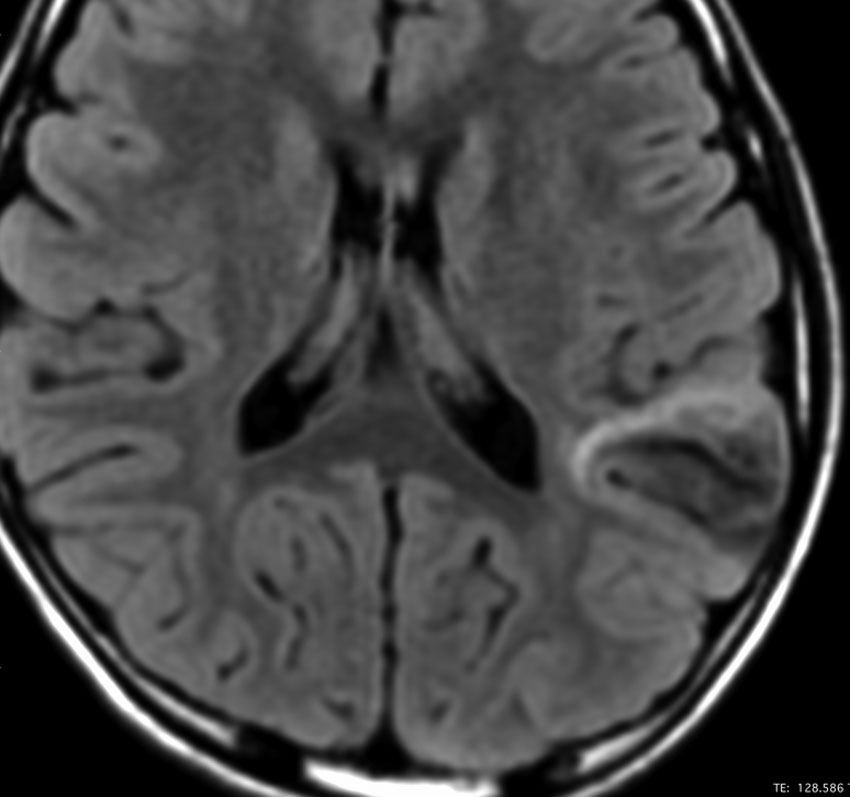

10歳でてんかん発症して難治性になった例

まだ日本にMRIが普及してなかった1988年,10歳でてんかん発作を発症しました。当時は,DNTという病名自体も知られていませんでした。これも典型的なDNTのMRI画像です。20代後半になって,複数の抗てんかん薬で治療を受けていましたが,難治性の発作をしばしば生じていました。発症してすぐに腫瘍摘出をしたほうがよかったのかもしれません。